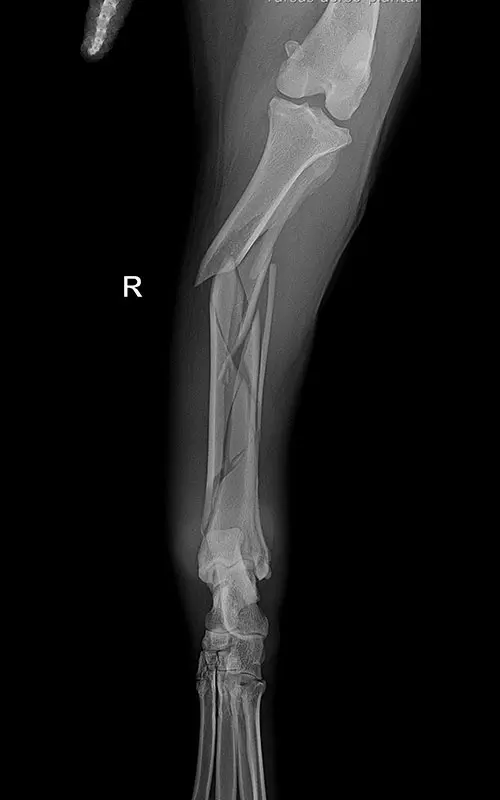

In our case, a 10-year-old labrador is involved in a car accident and his left femur and right tibia are severely injured. The dog had difficulty moving anyway due to severe hip arthrosis. During one surgical narcosis, K-pin - polyaxial locking plating was applied to both bones, the larger fragments were also fixed with 1-1 lag screws.

I intend the case to be initiated by anyone who has comments or remarks about the technique or the surgical procedure, I welcome it in a comment. I made a lot of mistakes…